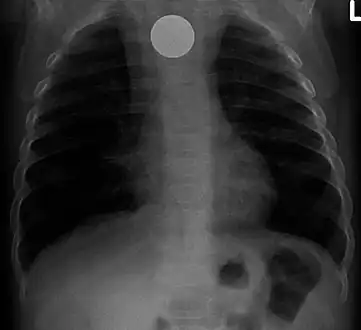

Multiple button batteries in the stomach

Button battery in the stomach

Both children and adults experience problems caused by foreign objects becoming lodged within their bodies. Young children, in particular, are naturally curious and may intentionally put shiny objects, such as coins or button batteries, into their mouths. They also like to insert objects into their ear canals and nostrils.[1] The severity of a foreign body can range from unconcerning to a life-threatening emergency. For example, a coin causes local pressure on the tissue but generally is not a medical emergency to remove. A button battery, which can be a very similar size to a coin, generates hydroxide ions at the anode and causes a chemical burn in two hours.[2] An ingested button battery that is stuck in the esophagus is a medical emergency. In 2009, Avolio Luigi and Martucciello Giuseppe showed that although ingested nonmagnetic foreign bodies are likely to be passed spontaneously without consequence, ingested magnets (magnetic toys) may attract each other through children's intestinal walls and cause severe damage, such as pressure necrosis, perforation, intestinal fistulas, volvulus, and obstruction.[3]